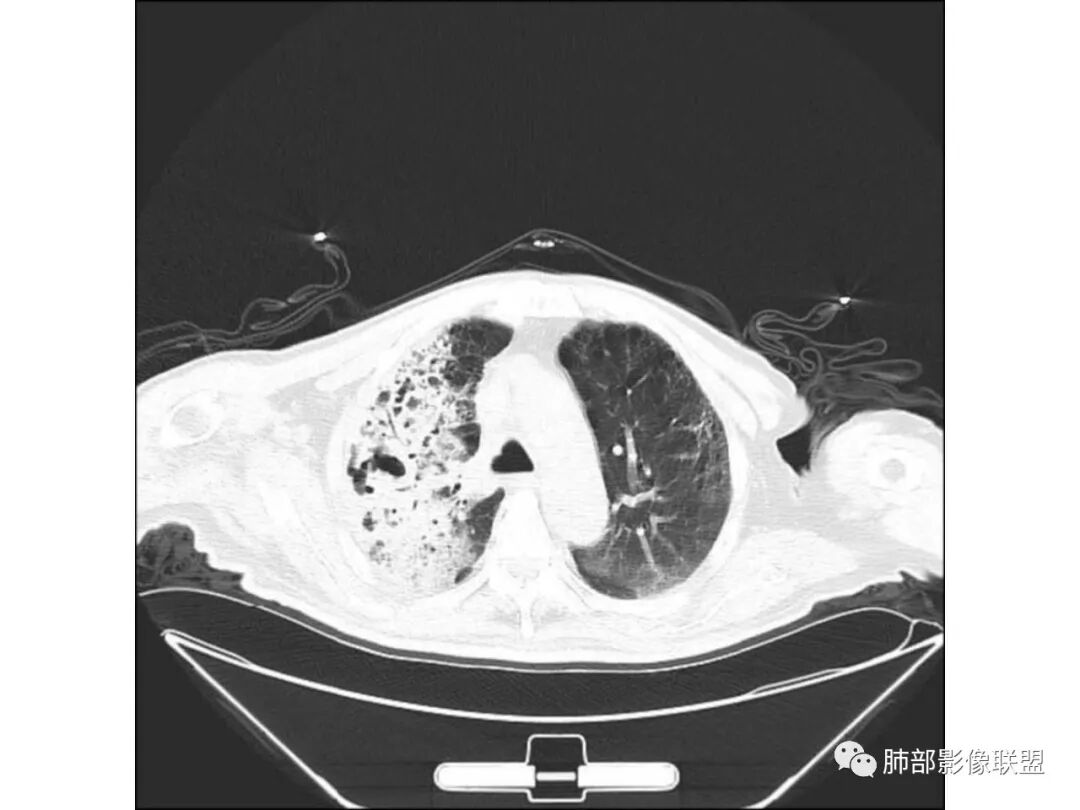

右肺上叶大片实变,其内可见虫蚀样空洞及扩张支气管,其中一空洞内可见曲菌球样结构,右肺体积略缩小。老年糖尿病患者,慢阻肺背景,考虑右肺上叶干酪性肺炎并曲霉感染。

老年糖尿病患者,右肺上叶大片状阴影,内见不规则空洞,内见结节,支气管壁增厚,其他肺野可见气囊影,考虑感染性病变,糖尿病患者常见的四大金刚(金毛结克),金黄色葡萄球菌感染,虽然有气囊,但是临床和其他影像不支持,毛霉菌感染,临床症状重,影像可见液平面,也不支持,肺克临床和影像表现不支持,考虑结核,待排结核合并曲霉菌感染。

老年男性,糖尿病基础,咳嗽,喘咳症状,病程10天,右上肺大片实变,以尖后段为主,实变内空洞影,支气管未见明显扩张,淋巴结肿大,首先考虑干酪性肺炎。但与干酪性肺炎不符的有临床症状轻,实变内支气管扩张不明显,没有树芽征,支气管播散。所以炎性肺癌待排;患者有肺气肿改变,肺气肿合并感染也在考虑范围,但左肺气肿不是十分重,放在第三位。总之,必须结合临床检验,治疗后复查。

老年男性,糖尿病基础,有咳嗽,喘累症状,病程10天,右上肺大片实变,内虫嗜样,无壁空洞,支气管壁增厚,扩张,淋巴结肿大,胸膜增厚,考虑干酪性肺炎,鉴别粘液腺癌。

老年男性,糖尿病病史,慢性病程,右胸廓塌陷,右肺沿支气管分布实变及GGO,叶段分布趋势,其内见支气管充气征及虫蚀样空洞,周围间质受累,指向气道来源病变播散,纵隔淋巴结肿大,密度高伴钙化,综合考虑干酪性肺炎。鉴别肺炎型肺癌。

老年男性,咳嗽气喘10天,双肺明显肺气肿,右上肺叶实变,内见大量空洞及囊腔样改变(部分为支气管扩张),实变区周围表现为网格样改变,有明显的小叶间隔增厚,边界似清非清,支气管走行僵硬,有枯树枝样改变,双下肺胸膜下小叶间隔增厚明显,边缘相对模糊,综合考虑如下:1、粘液腺癌可能大(枯树枝样改变,边界似清非清,小叶间隔增厚符合)。2、结核,右上肺似像干酷样改变,内有空洞及支扩样改变支持,但下肺及左肺无相关支气管播散的小叶中心结节及树芽,不支持,临床病症不支持,只有咳嗽,喘气,无咳痰及结核中毒症状。当然结核是妖,需要结合痰检及结核相关指标进一步明确。3、肺克,虽有10年糖尿病史,但肺部只有右肺改变明显,无胸膜下脓肿表现,无脓毒栓表现,临床症状也不支持。4、其他感染?双下肺胸膜下病灶边缘模糊,不完全除外,需要结合临床炎性指标分析。

右上肺大片状高密度影,呈蜂窝样改变,部分气腔无壁,部分呈厚壁改变,内部结构紊乱,部分边缘GGO边界清楚,大小不一,病灶近端小远端大,近端支气管壁增厚,支持感染性病变,考虑结核,其内支气管呈枯树枝改变,病灶局部膨隆,内部结构紊乱,边界的GGO部分清楚,恶性(腺癌)待排。

老年男性,糖尿病病史,咳嗽咳痰10余天入院。右上肺实变,见支气管充气征,部分支气管扩张,虫蚀样空洞,无壁空洞内壁光滑,实变病灶内见粘液成分,右上肺体积稍缩小,结核和肺炎性肺癌的鉴别,结核可能大,合并间质性肺病。